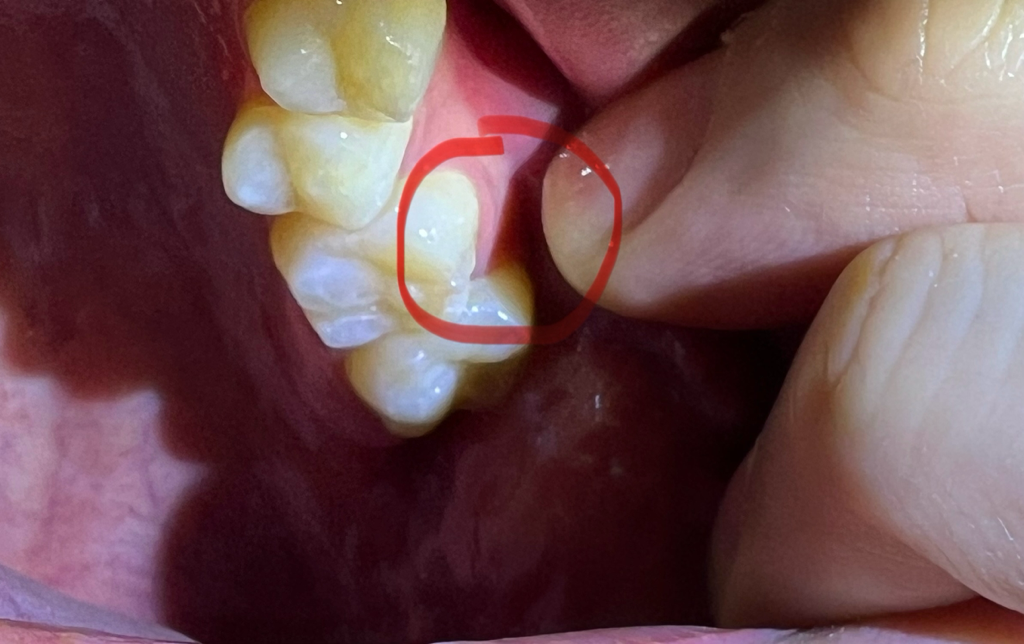

양치할때 통증은 없습니다만

의도적으로 그 부위에 바람을 넣거나

손톱으로 깨진부위 안쪽을 살살 두드리면 이가 시립니다

• 3번 째 사진

치아가 어느정도 깨지신거 같은데 시리시다면 신경치료를 하셔야될수도 잇고 치아 상태에 따라 크라운 치료를 하셔야될수도 있습니다.

치과 가기전까지는 차거나 뜨거운 음식 등 자극적인 음식을 피하시고 딱딱하거나 질긴 음식도 피하시기 바랍니다.

현재 치과를 방문하기가 어려운 경우에는 우선 해당치아로 단단하거나 끈적이는 음식 섭취는 피하길 권하며, 한국에 방문하여 빠른시일내에 방문하여 상태를 확인하고 치료를 받길 권합니다.